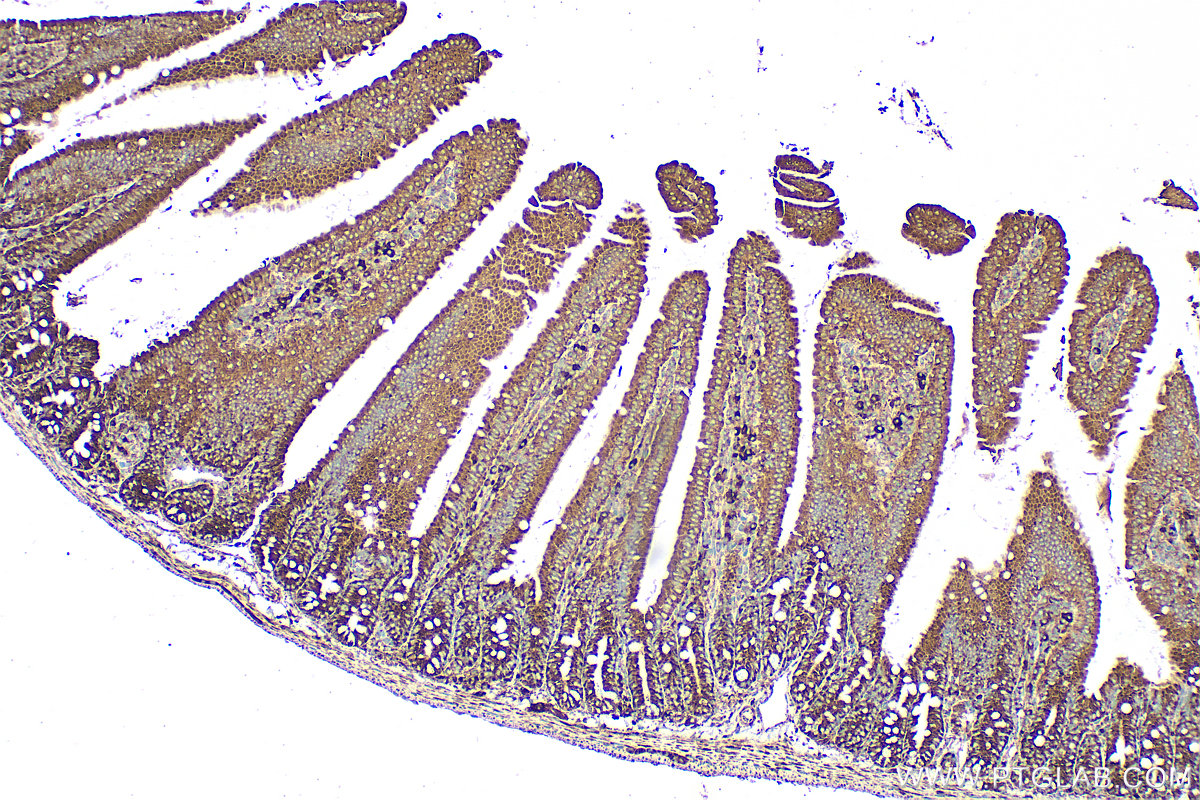

| Positive IHC detected in | mouse small intestine tissue, human brain tissue, human small intestine tissue Note: suggested antigen retrieval with TE buffer pH 9.0; (*) Alternatively, antigen retrieval may be performed with citrate buffer pH 6.0 |

| Immunohistochemistry (IHC) | IHC : 1:50-1:500 |